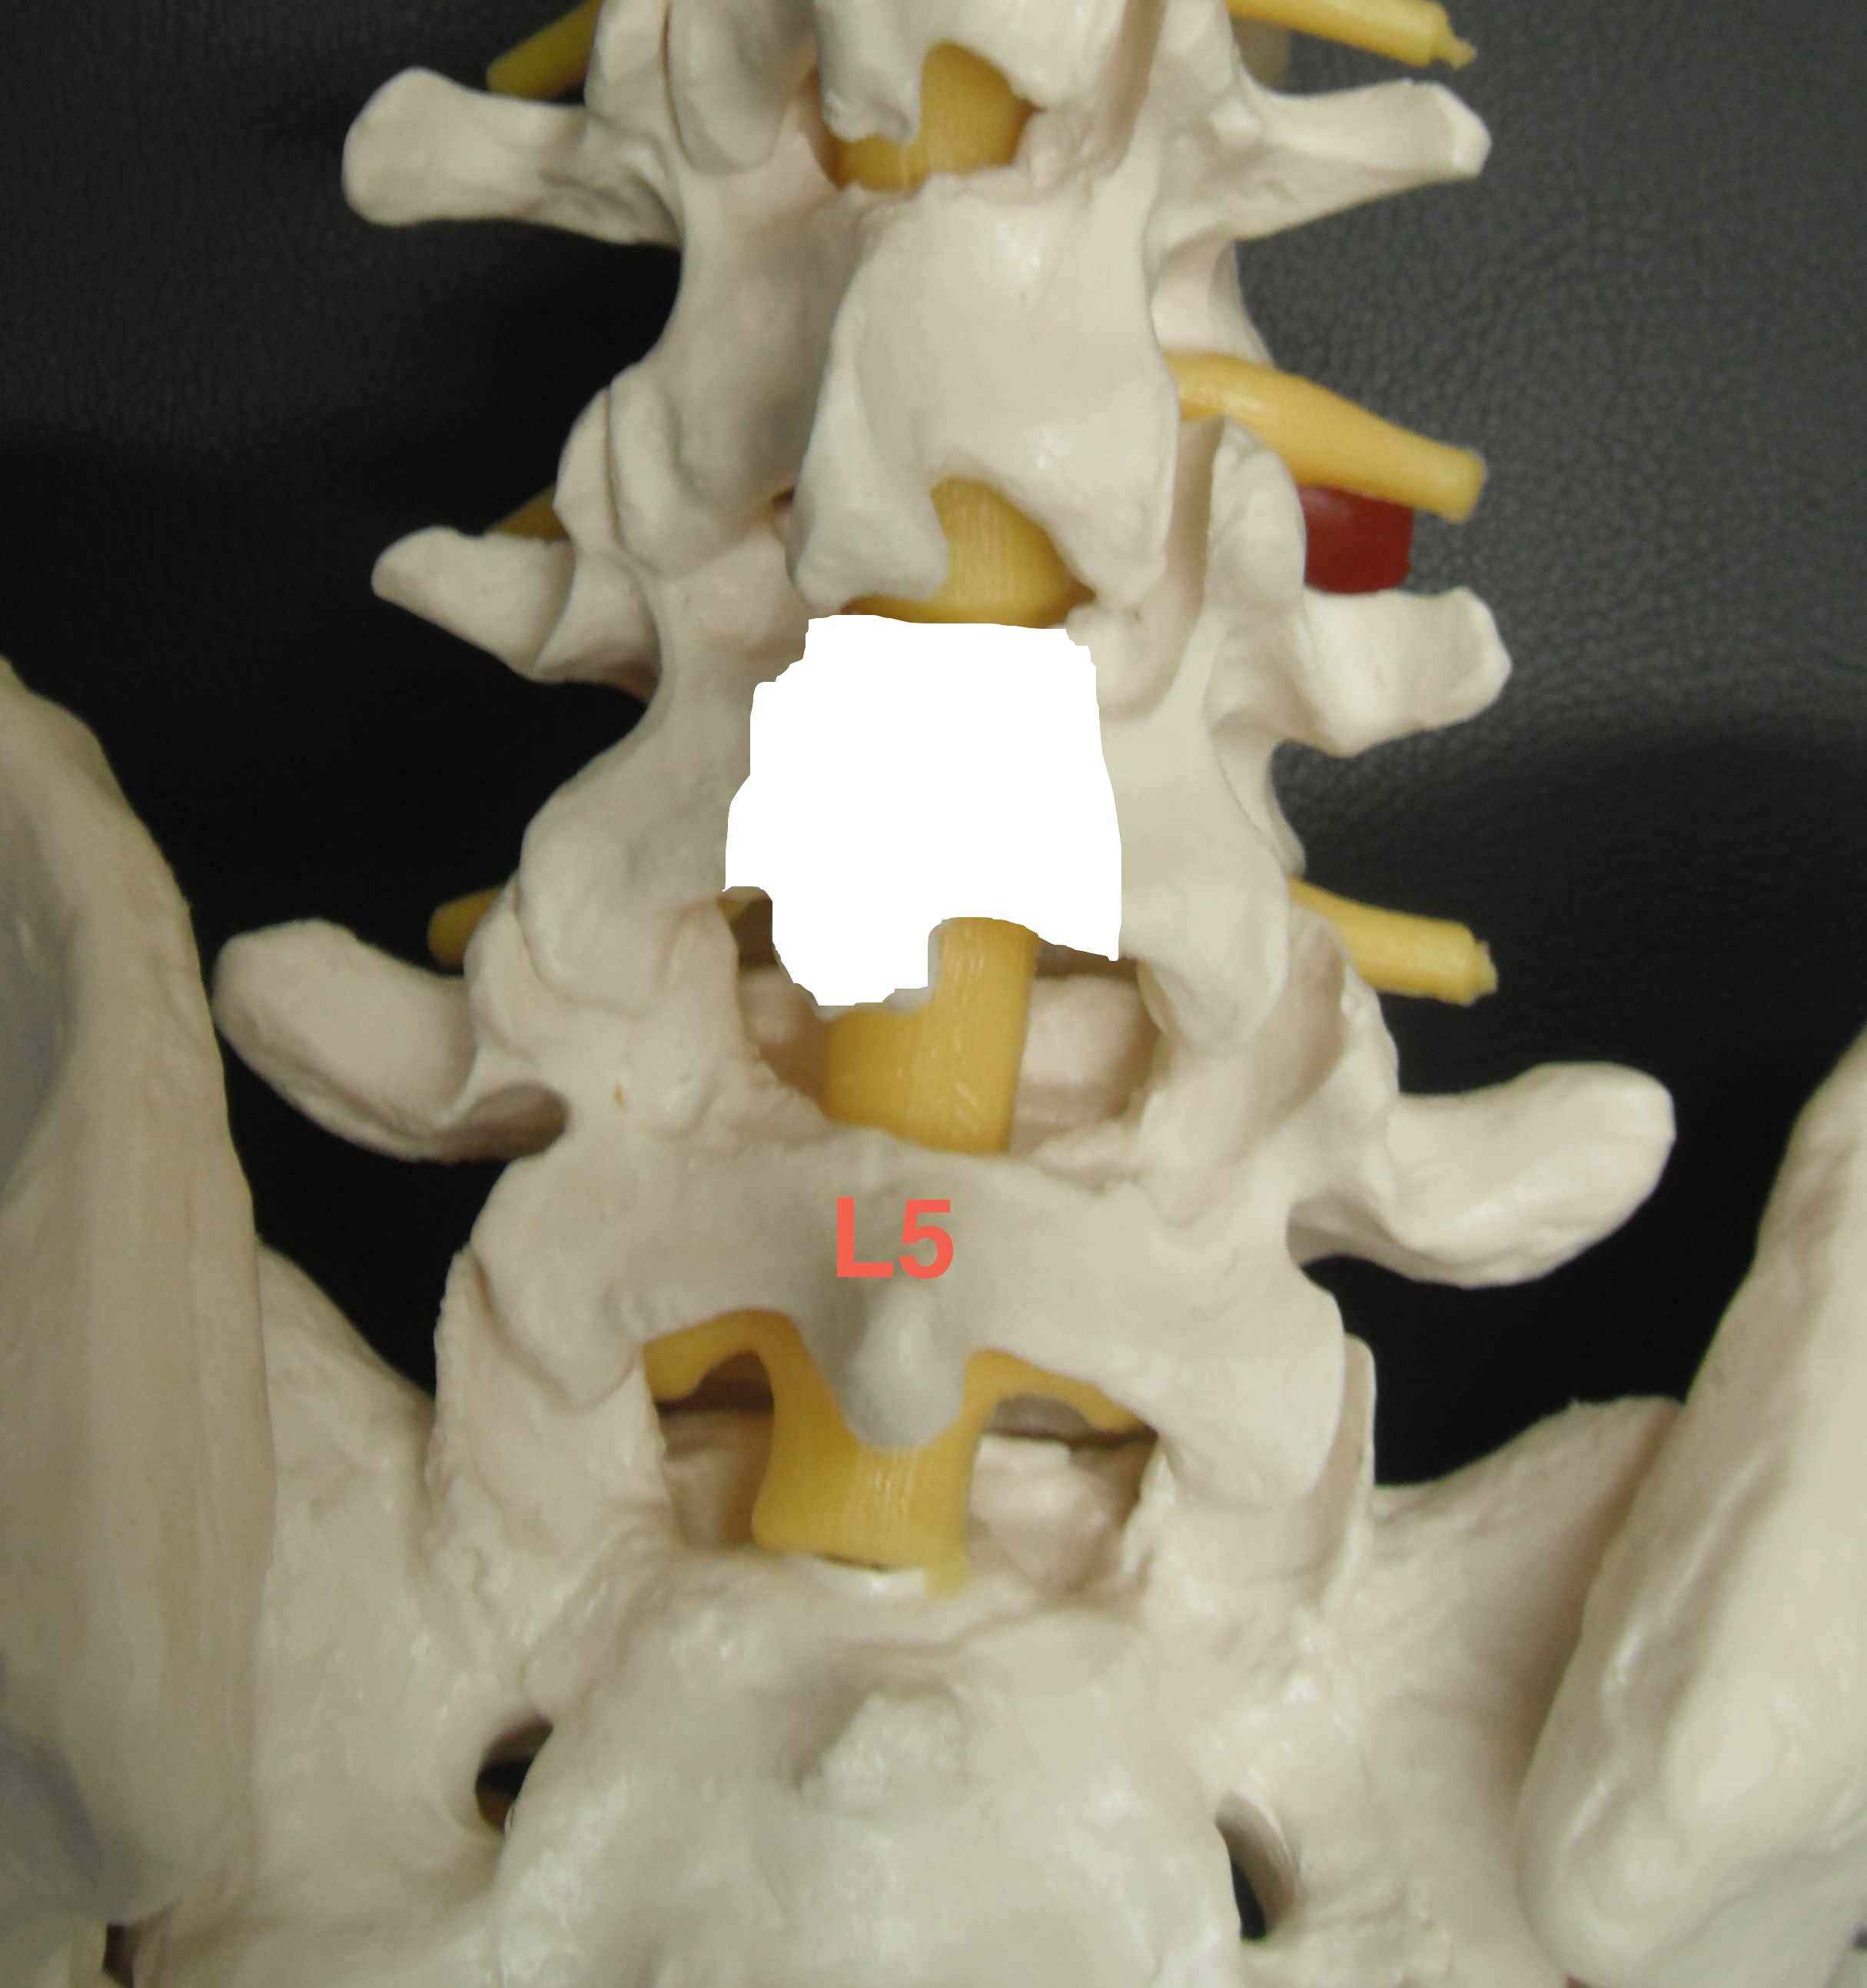

- L5 most common, then S1

L3/4 & L4/5 most common